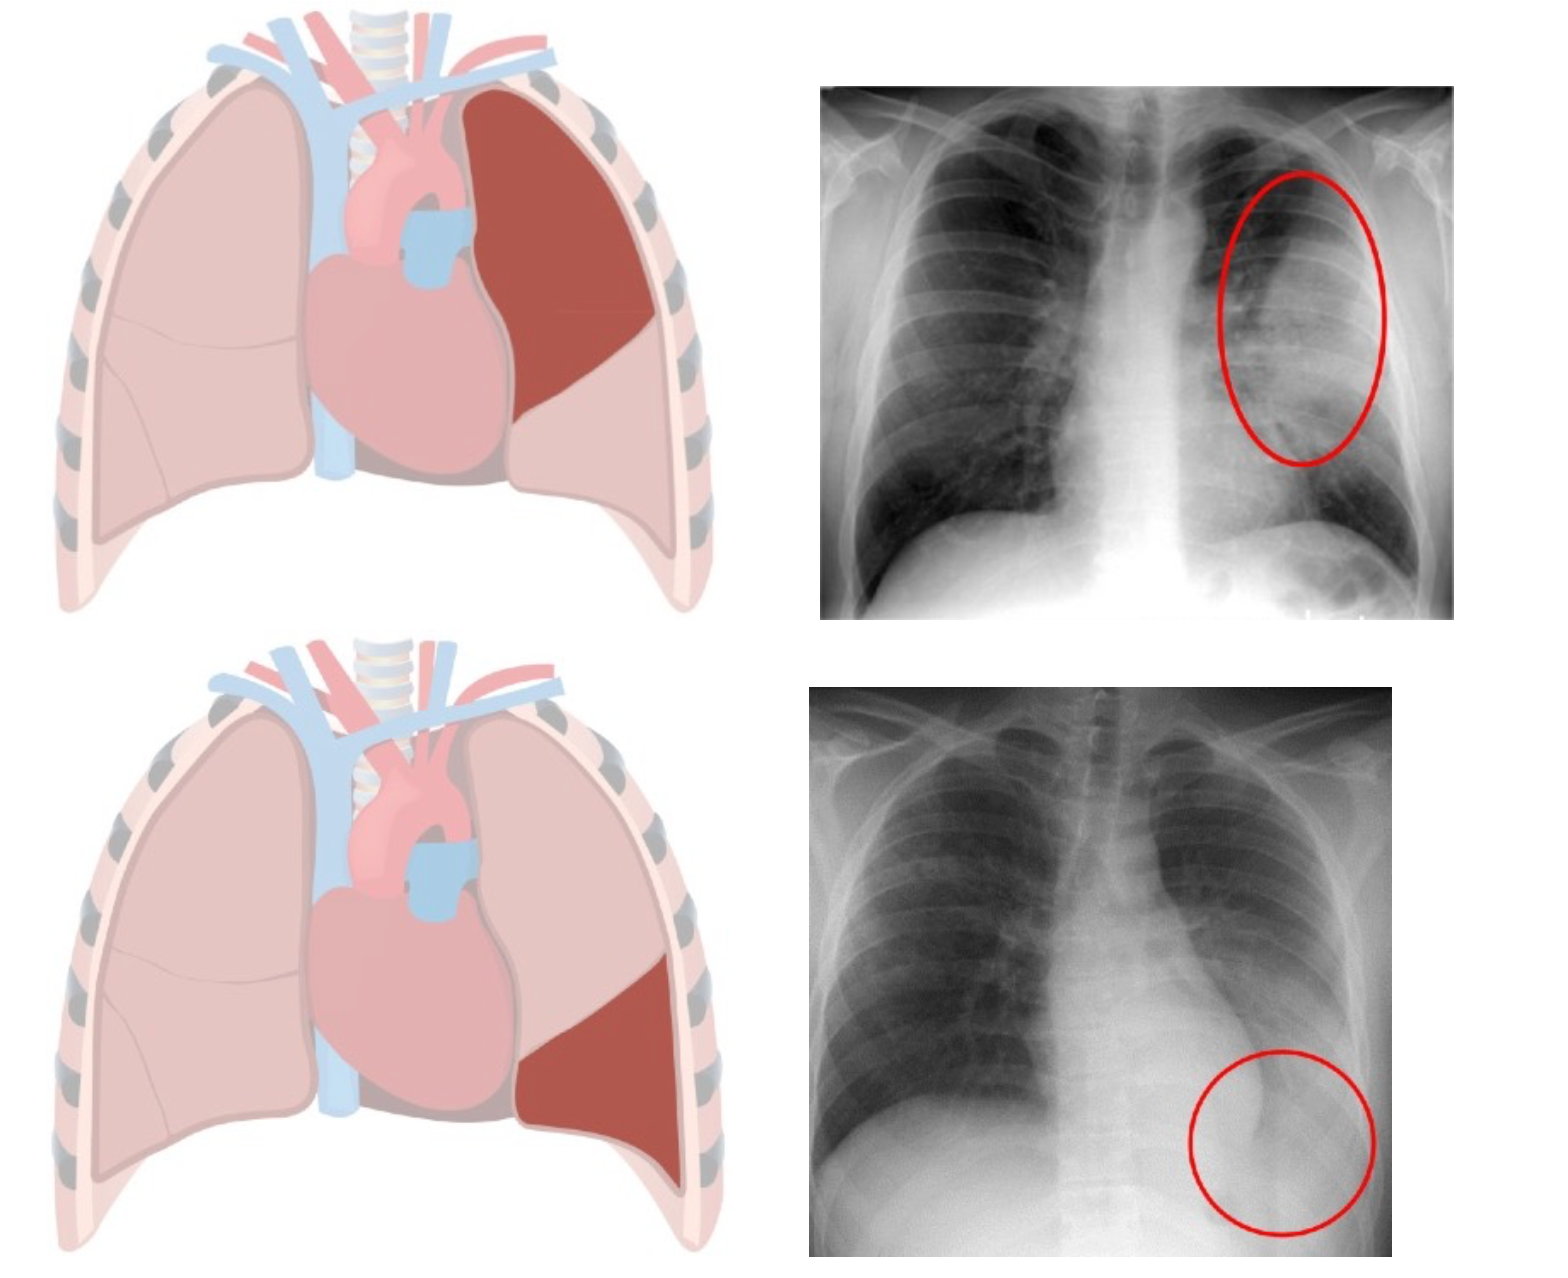

Chest x-ray helps to diagnose lobar pneumonia. The x-ray will show the pus and other substances in the affected lung lobe, which has a cloudy white appearance on the x- ray. Here are some examples of chest x-rays showing infection in different lobes: